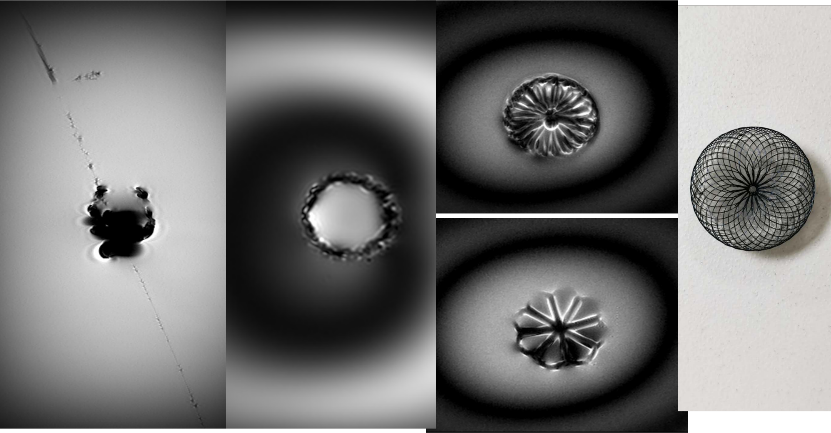

血管支架MR兼容性测定-SE,FFE状态下测伪影 封堵器MR兼容性测定SE,FFE状态下测伪影